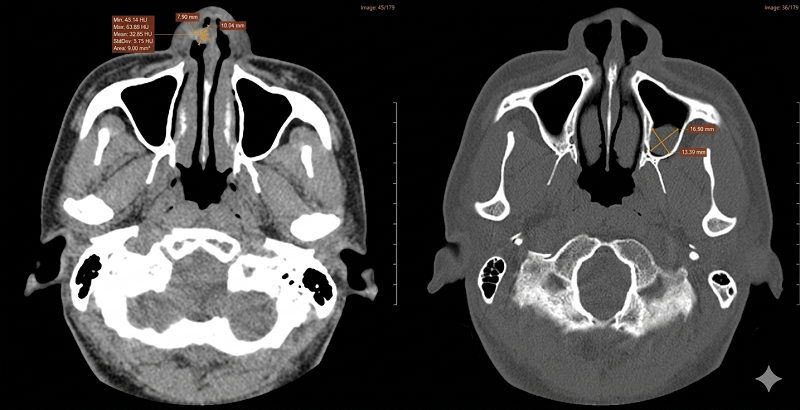

Chụp CT xoang phát hiện Polyp xoang hàm trái, nốt khu trú tiền đình mũi phải

- Chụp cắt lớp vi tính (CT-scanner) xoang: Ghi nhận tình trạng viêm đa xoang mức độ II theo phân loại Lund-Mackay, dày niêm mạc cuốn mũi hai bên, polyp xoang hàm trái và nốt khối khu trú tại tiền đình mũi phải.